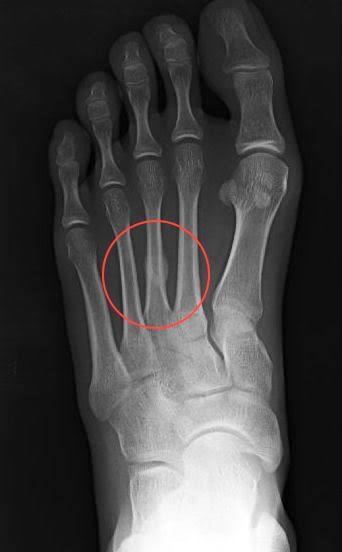

行軍骨折は中足骨の疲労骨折で、下肢の疲労骨折のなかで脛骨の次に多く見られる骨折です。“行軍骨折”という名称は、軍隊の長距離の行軍中に発症することが多かったことに由来しています。

スポーツ障害として生じることが多く、第2および第3中足骨骨幹部によく見られます。特に陸上競技、バスケットボール、バレーボール、剣道などで多くみられます。また、第2中足骨基部の疲労骨折はバレエダンサーに多く、ポアントの肢位でのジャンプ動作を繰り返すことによ

って起こります。

中足骨の疲労骨折はランニング動作やジャンプ動作を繰り返すことによって、横アーチが地面から受ける衝撃と足底筋群の牽引力によるたわみが繰り返される為に、発症すると考えられます。